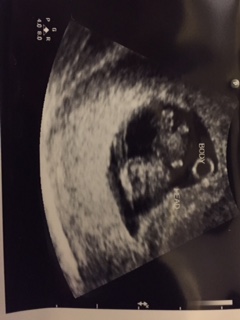

6w4d. Heartbeat at 140. Tech said ultrasound was messing up a bit, which could explain the "mirror twin". Guess we have to wait and see! (Anyone else have this issue?)

Tech said ultrasound was messing up a bit, which could explain the "mirror twin". Guess we have to wait and see! (Anyone else have this issue?)